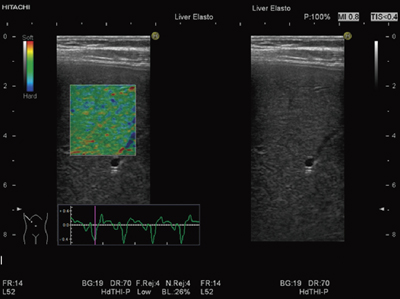

肝臓領域でReal-time Tissue Elasto-graphyを施行する際は,プローブによる圧迫は行わずに,心拍動によるひずみを利用する。被検者に息止めをしてもらい,心拍動に合わせて周期的にReal-time Tissue Elastographyが描画されることをStrain Graphにて確認する。Strain Graphは,組織のひずみの時間変化を表示したもので,リアルタイムに圧迫の状態をグラフ表示することにより,より安定したReal-time Tissue Elastographyの描出をサポートするものである。

スキャン方法は,右肋間走査が最適であり,描出される肝右葉のBモード画像を詳細に観察して,横方向の変位が少なく,Real-time Tissue Elastographyの演算に必要な深度方向の変位を検出できる断面で撮像することが望ましい(図2)。また,注意点として,血管壁周辺や肝表面の多重エコー,および肋骨のシャドーなどによるアーチファクトは計測に影響を及ぼす可能性があるため,Real-time Tissue ElastographyのROIからは避けることが望ましい。

■Strain Histogram計測ソフトによる画像解析

Real-time Tissue ElastographyのStrain Histogram計測ソフトによる画像解析について述べる。画像解析を行うために最適なフレームの探索が必要であるが,Strain Graphを用いてフレームを選択することで,1心拍中に一度心臓によって圧迫された肝臓が弛緩する時相を見つけることができる。その時相は,ひずみが最も大きく,安定したElasto-graphyを描出することが可能である。

Strain Histogram計測は,ROI内の任意に指定された領域の相対ひずみ値のヒストグラム(頻度分布のグラフ)を表示するもので,テクスチャー解析によるReal-time Tissue Elastography画像の特徴量の算出も可能である(図3)。

図3 Strain Histogram計測ソフトによる画像解析